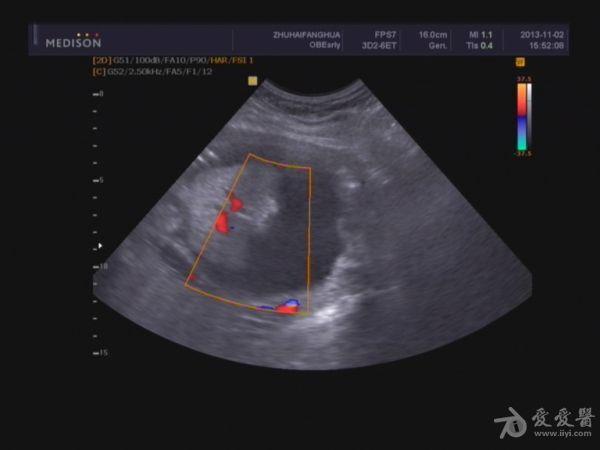

脐带:结构正常,脐动脉血流参数:SPV:33cm/s,PI:1.0,RI:0.62,S/D:2.6。典型图片如下:

单胎妊娠;臀位,颅骨环基本完整,脑中线居中,CER: 24mm,CM:不清,双侧丘脑可见,侧脑室未见明显扩张,小脑可显示欠清,胎儿颈项部欠清,胎儿颜面显示不清,胸腔增大内见积液,腹壁完整,肝、可见,腹腔内大量积液,最大径约:71mm,胸腔内积液最大径:11.4mm,胃及膀胱显示不清。双肾显示不清。双侧四肢长骨显示欠清。

2.胎儿畸形,胸、腹腔大量积液,